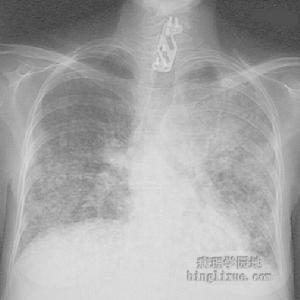

其他輔助檢查:X線表現:枸櫞酸桿菌肺炎的胸片主要表現為支氣管肺炎,可為局灶性浸濕陰影或瀰漫性雙側下肺浸潤陰影,肺小膿腫。胸腔積液及膿胸較少見。